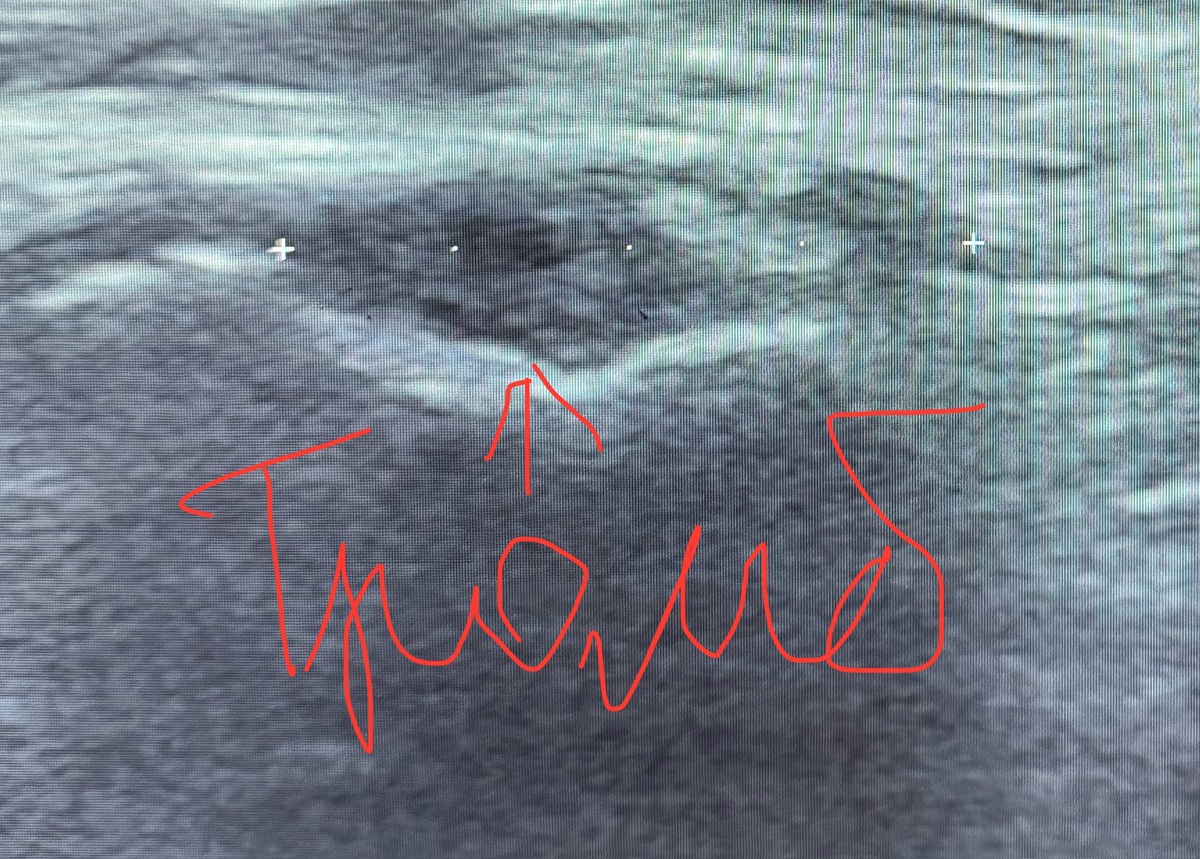

⌨️ УЗИ вен нижних конечностей с допплерографией – золотой стандарт диагностики ТГВ, помогает увидеть сам тромб.